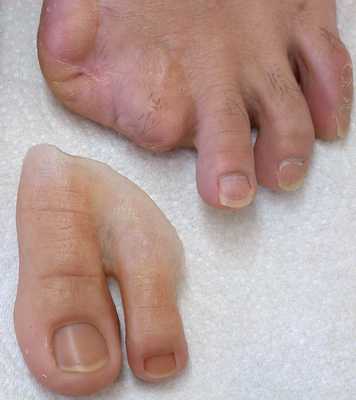

Ампутация пальца

Ампутация пальца - операция по удалению пальца при его некрозе или гангрене. Является частным элементом некрэктомии при гангрене. Выполнять ампутацию фаланги пальца можно лишь тогда, когда есть уверенность в достаточном кровообращении остающихся тканей. Только при данном условии рана после удаления пальца заживет, в противном случае можно ожидать прогрессирования некротического процесса.

- Удаление пальца может проводиться с пересечением фаланговых или плюсневых костей, тогда операция называется ампутацией, либо проводится вычленение пальца в суставе - экзартикуляция.

Осложнения хирургического лечения

Так как ампутация пальца ноги или руки является небольшой по объему операцией, то риск для жизни невелик. Основные осложнения после вмешательства развиваются при неправильном определении показаний к этой операции. Если ампутация проводится на уровне тканей с плохим кровоснабжением, то рана после такой ампутации никогда не заживет, а напротив нагноится и будет распространяться дальше. В такой ситуации необходимо произвести повторную операцию на более здоровых тканях. На руках, выполняя ампутацию пальцев кисти необходимо стремиться к максимальному сохранению длины и функциональности, не выходя за пределы пястной кости, так как рука - основной рабочий инструмент в жизни человека.